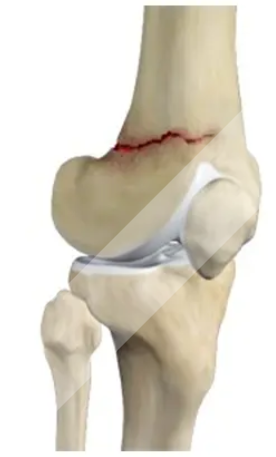

Total Knee Replacement

Anterior Cruciate Ligament Tear

Medial Collateral Ligament Injury

Lateral Collateral Ligament Injury

Posterior Cruciate Ligament Injury